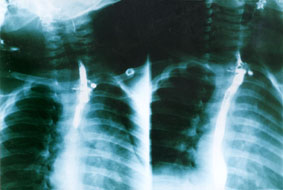

La mattina dopo viene fatta una prima radiografia in bianco, nell'ipotesi di un corpo estraneo esofageo, con esito negativo, e subito dopo una radiografia con mezzo di contrasto (v. figura) che evidenzia una immagine che, sulle prime, fa pensare ad un diverticolo esofageo, ma che l'indagine endoscopica successiva dimostra essere lo stampo di un corpo estraneo disposto trasversalmente al limite fra il terzo superiore e il terzo medio dell'esofago.

L'immagine del falso diverticolo era riconducibile alla raccolta di un po' di bario fra la parete dell'esofago e uno dei lati minori del corpo estraneo, che era un pezzo di plastica di quelli che si trovano nelle uova di cioccolata.